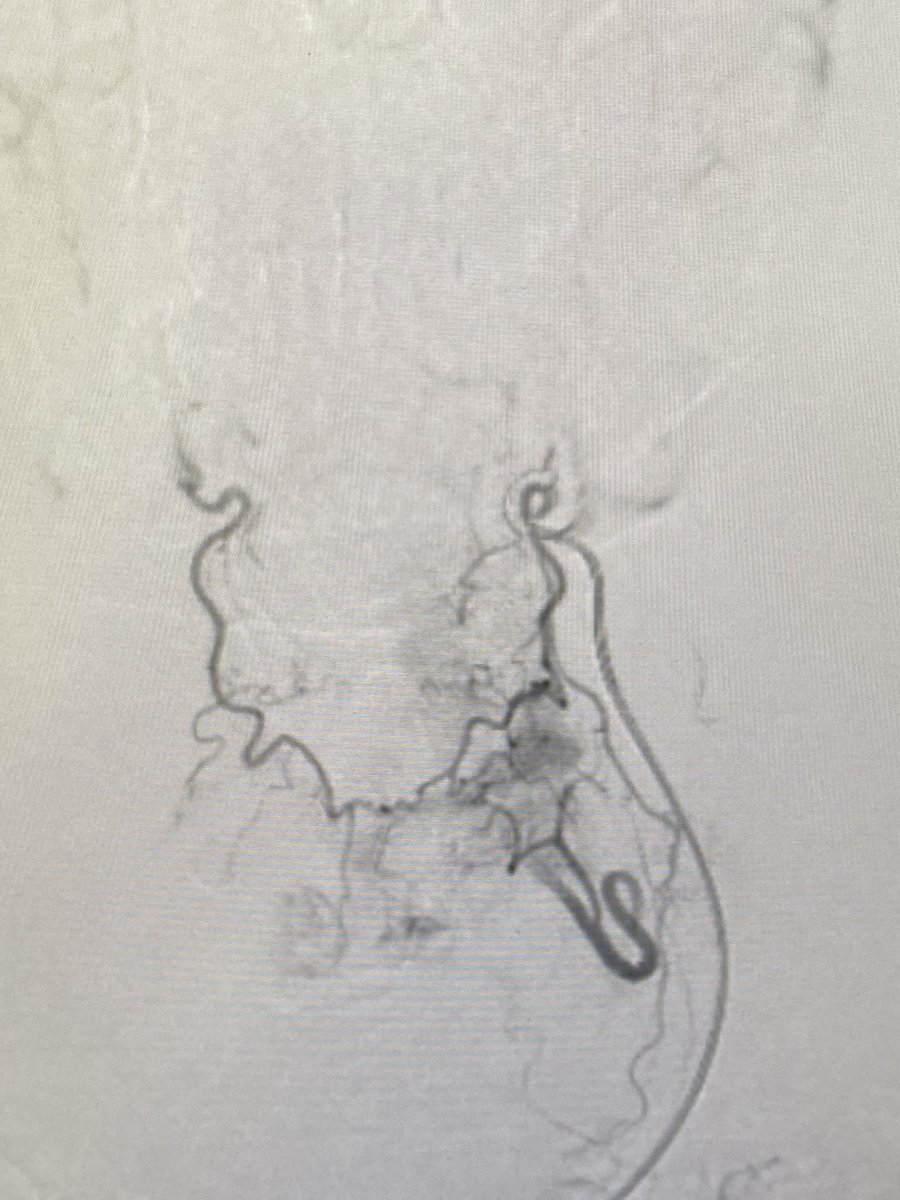

Two weeks ago, a 54-year-old patient recovering from open-heart surgery (CABG) suffered a major stroke. • Symptoms: Sudden inability to speak + right-side paralysis. • Action: Immediate Mechanical Thrombectomy to remove the brain clot.

Manish Kumar Yadav tweet mediaManish Kumar Yadav tweet mediaManish Kumar Yadav tweet mediaManish Kumar Yadav tweet media